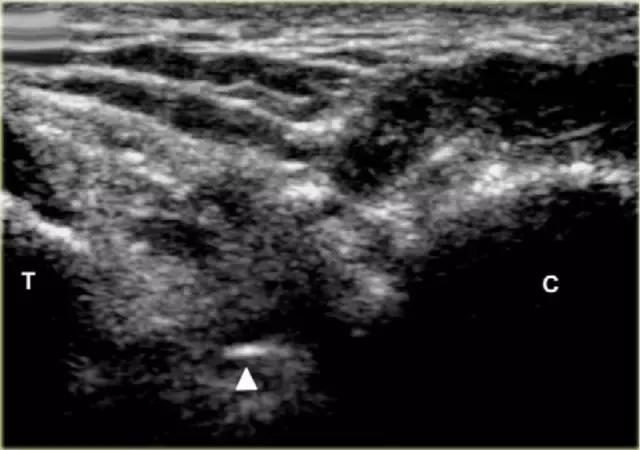

超声引导的跗骨窦的注射在右手侧与外侧入路。探头保持在冠状倾斜平面中。针沿着探头的长轴引入。

使用超声波可以容易地观察窦性骨壁。患者转向对侧,将待治疗的足以其内侧表面靠在桌面上,脚的外侧位于最上面。探头保持在关于脚的冠状平面中。

在跗骨窦被识别为跟骨的前处理和距骨颈之间的三角空间。针(箭头)的前端的锥形跗骨窦,这是由距骨(T)和跟骨(C)的边界内可以看到。

根据炎症的程度,可能存在空间的充血,并且可能存在中间血管可见,这是人们希望避免的。但是这又是比较容易的,特别是彩色多普勒。